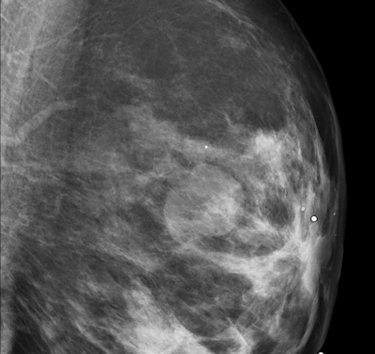

At the same time, dense tissue makes abnormalities more difficult to read, especially on traditional film-screen mammography. The landmark Digital Mammographic Imaging Screening Trial (DMIST) demonstrated better detection of dense-breast abnormalities using full-field digital mammography (area under the curve [AUC] 0.78 ± 0.02) versus film-screen mammography (AUC 0.68 ± 0.03).

"Dense breasts can mask cancer that's there, reducing contrast," Astley said. "Its effect on CAD isn't clear-cut; there is conflicting evidence in the literature. Some say it tends to reduce the performance of CAD, while other work shows no effect."